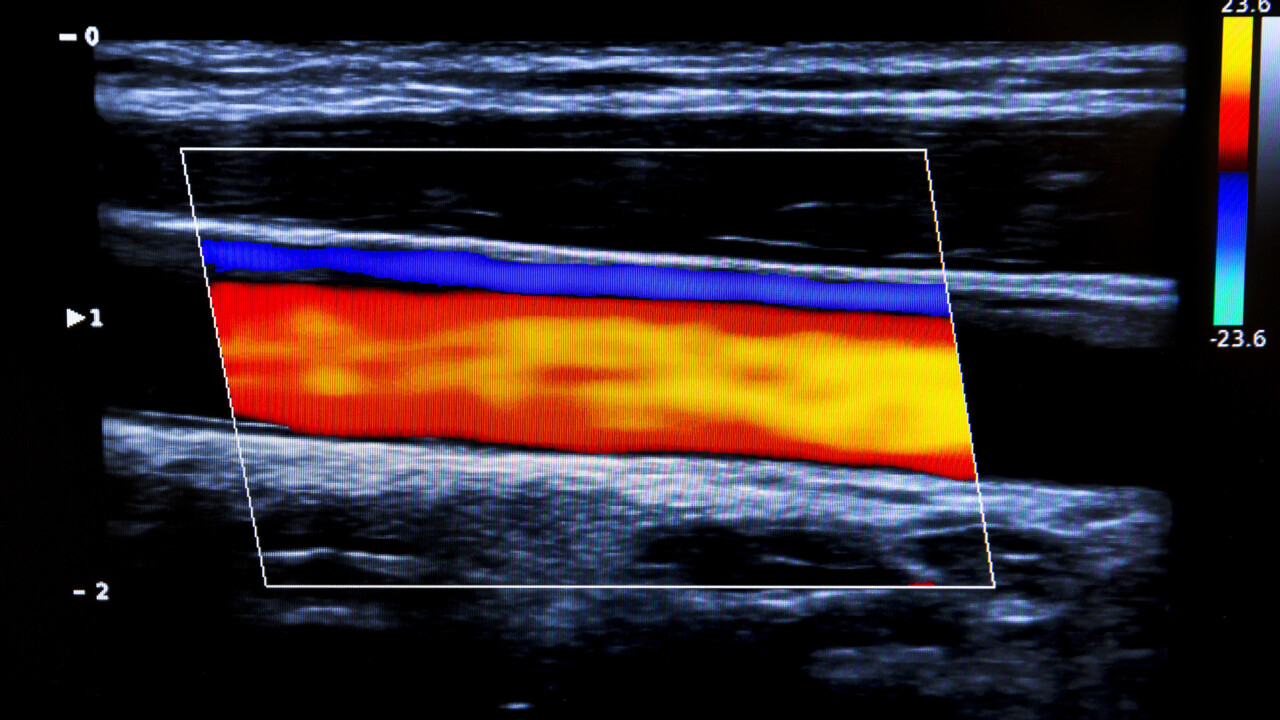

NYHET Forskningsstudien Västerbottens digitala tvilling får en donation på tre miljoner kronor per år i två år av den Umeå-baserade stiftelsen Fort Knox.

"Västerbottens digitala tvilling" syftar till att utveckla nya och mer individualiserade metoder för effektivare förebyggande insatser mot hjärt-kärlsjukdom. Forskningen ska använda omfattande data från Västerbottens Hälsoundersökningar och den pågående Vipviza-studien i utvecklingen av bland annat digitala hjälpmedel till stöd för individen att uthålligt förändra levnadsvanor och följa rekommenderad förebyggande behandling.